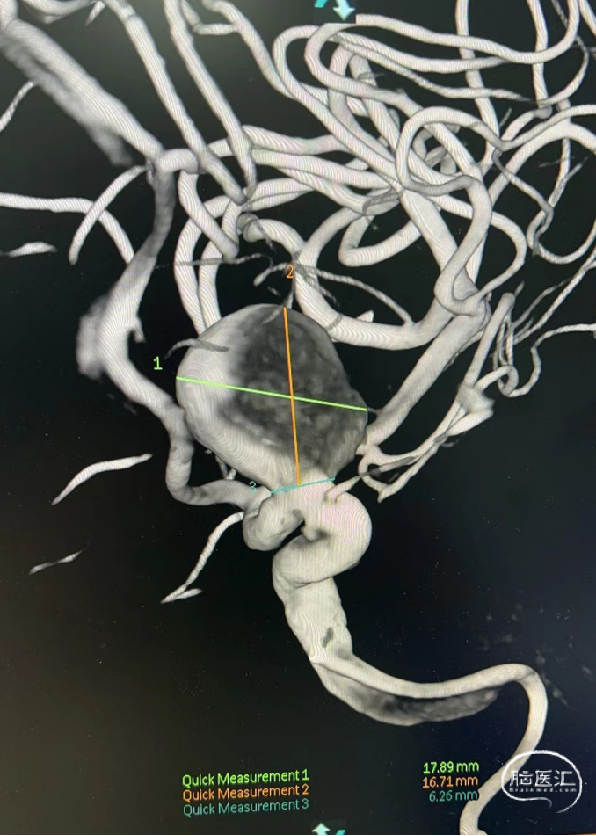

现病史:患者1周前因头晕来我院就诊,完善头MRI+CTA等检查,诊断为:左侧颈内动脉C6段动脉瘤(大小约16*17mm),宽颈。为进一步治疗入住我科。

术前造影可见左侧颈内动脉C6段动脉瘤,大小约17.89×16.71mm,瘤颈宽约6.26mm。